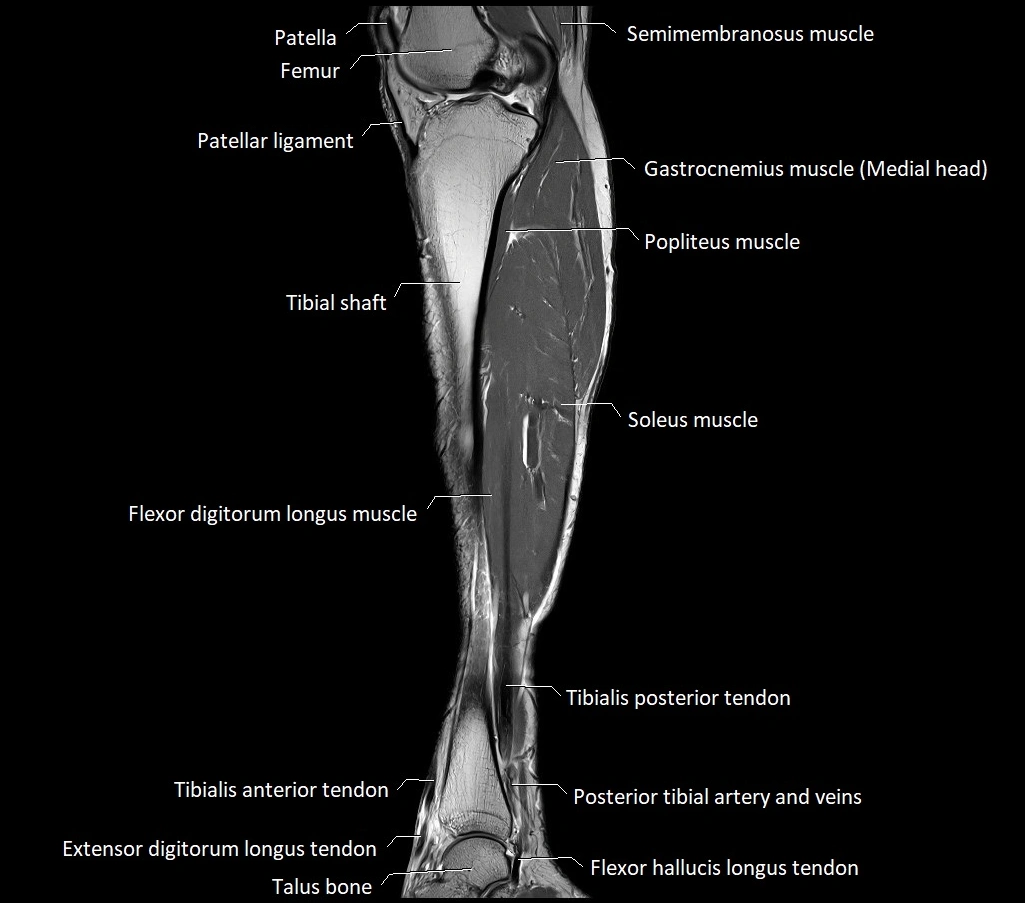

MRI image